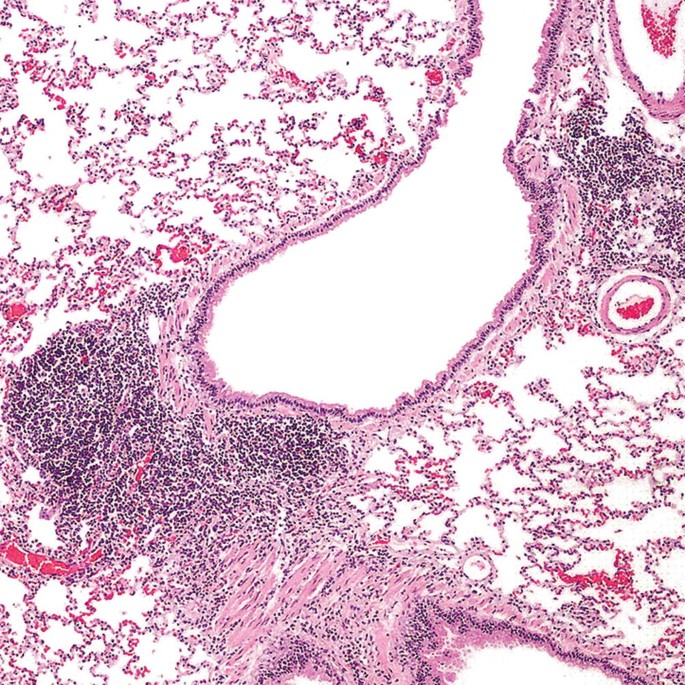

Malignant Hematopoietic Disorders of the Lung | SpringerLink